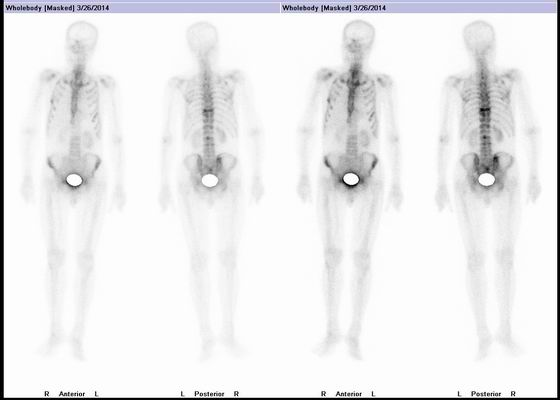

上圖為全身骨顯像

第三可以對全身骨骼進行顯像,一次顯像就能顯示全身骨骼病變,可以進行惡性腫瘤患者腫瘤骨轉(zhuǎn)移的早期診斷,也可以探查骨、關(guān)節(jié)炎性病變和退行性病變等,還可以評價骨病治療前后的療效;

在《關(guān)于唐醫(yī)生的一切》劇中所說的放射性核素全身掃描其實是指:PET/CT腫瘤顯像或者是SPECT/CT全身骨顯像,二者均可一站式檢出全身有無轉(zhuǎn)移性病灶,只是SPECT/CT全身骨顯像只能檢出骨骼轉(zhuǎn)移灶。